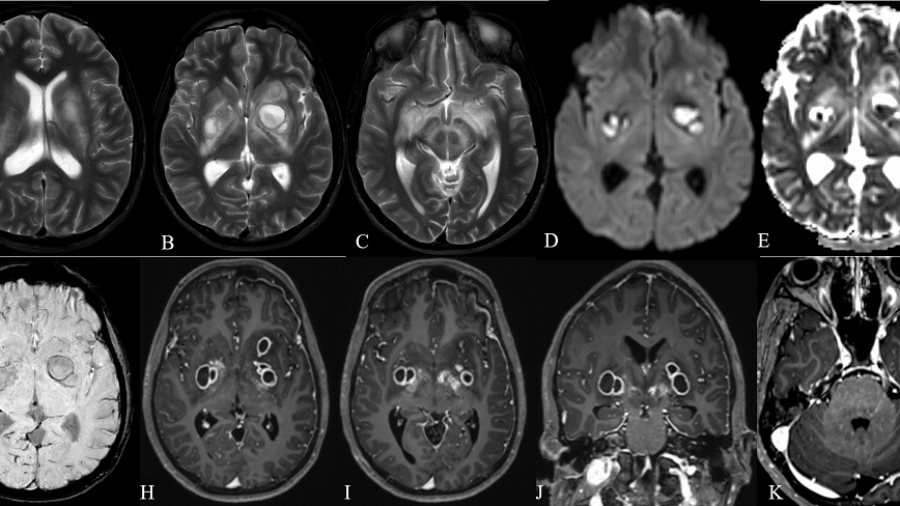

50 year old man presented with history of pyrexia of unknown origin, dull headache ,right ear pain, left side weakness and difficulty in swallowing. On neurological examination: Right side diplopia on looking at far objects